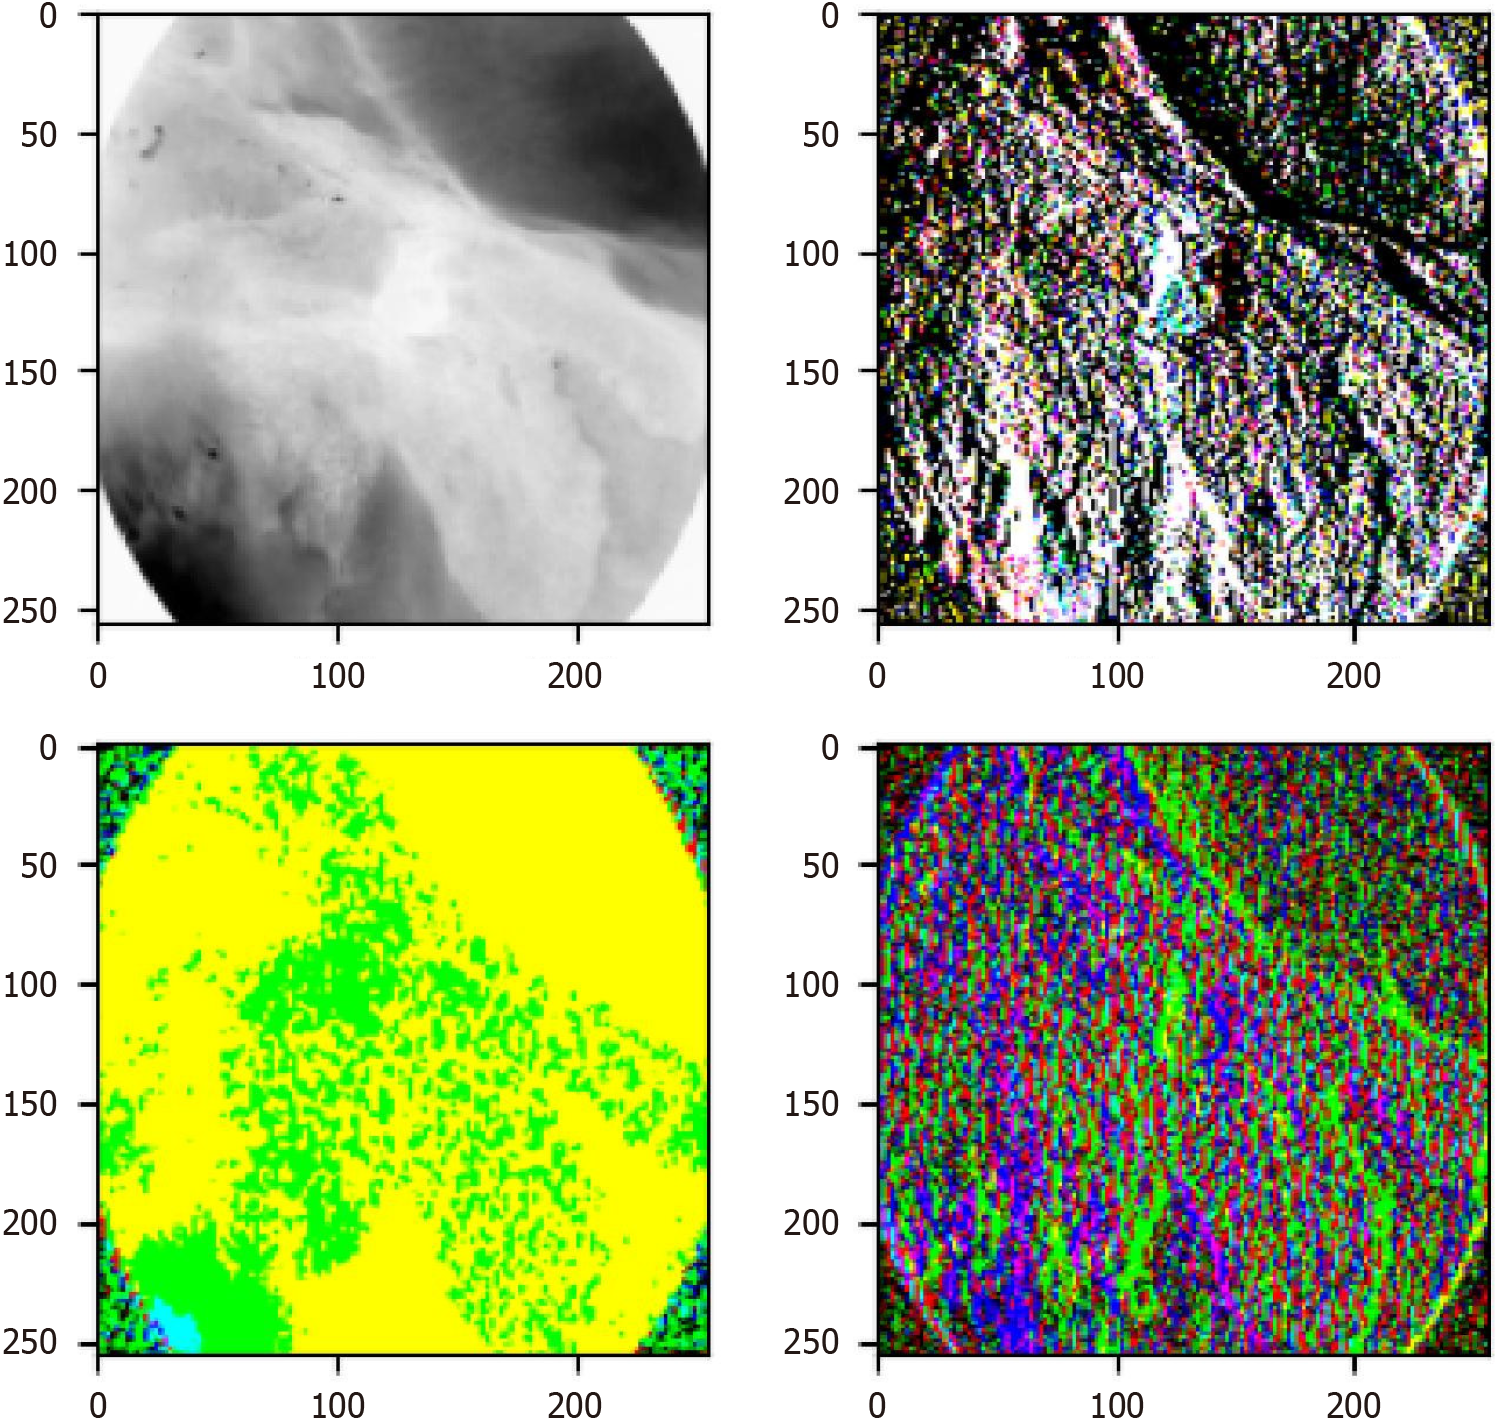

To further analyze how the wavelet block in Wave-ViT extracts frequency domain features, this study visualizes the first wavelet block’s feature extraction process, as shown in Figure 8. The wavelet block employs a fundamental time-frequency analysis method, decomposing the input signal into different frequency sub-bands - namely, low-frequency components (top-left in Figure 8) and high-frequency components (top-right, bottom-left, and bottom-right in Figure 8) - to address aliasing issues. Specifically, the low-frequency component reflects the coarse-grained structure of basic objects, while the high-frequency components retain fine-grained texture details. In this way, various levels of image detail are captured in the extracted feature maps without information loss.

The Wave-ViT model incorporates wavelet transform to leverage frequency domain decomposition, significantly improving the detection of EAC lesions. Wavelet transform allows the model to conduct multi-scale analysis in the frequency domain, enabling effective feature extraction across different frequency bands[39]. Specifically, the model first applies wavelet transform to decompose EAC images (e.g., biopsy tissue slides or medical scans) into low-frequency and high-frequency components: Low-frequency components retain global structural information. High-frequency com